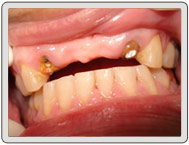

治療前